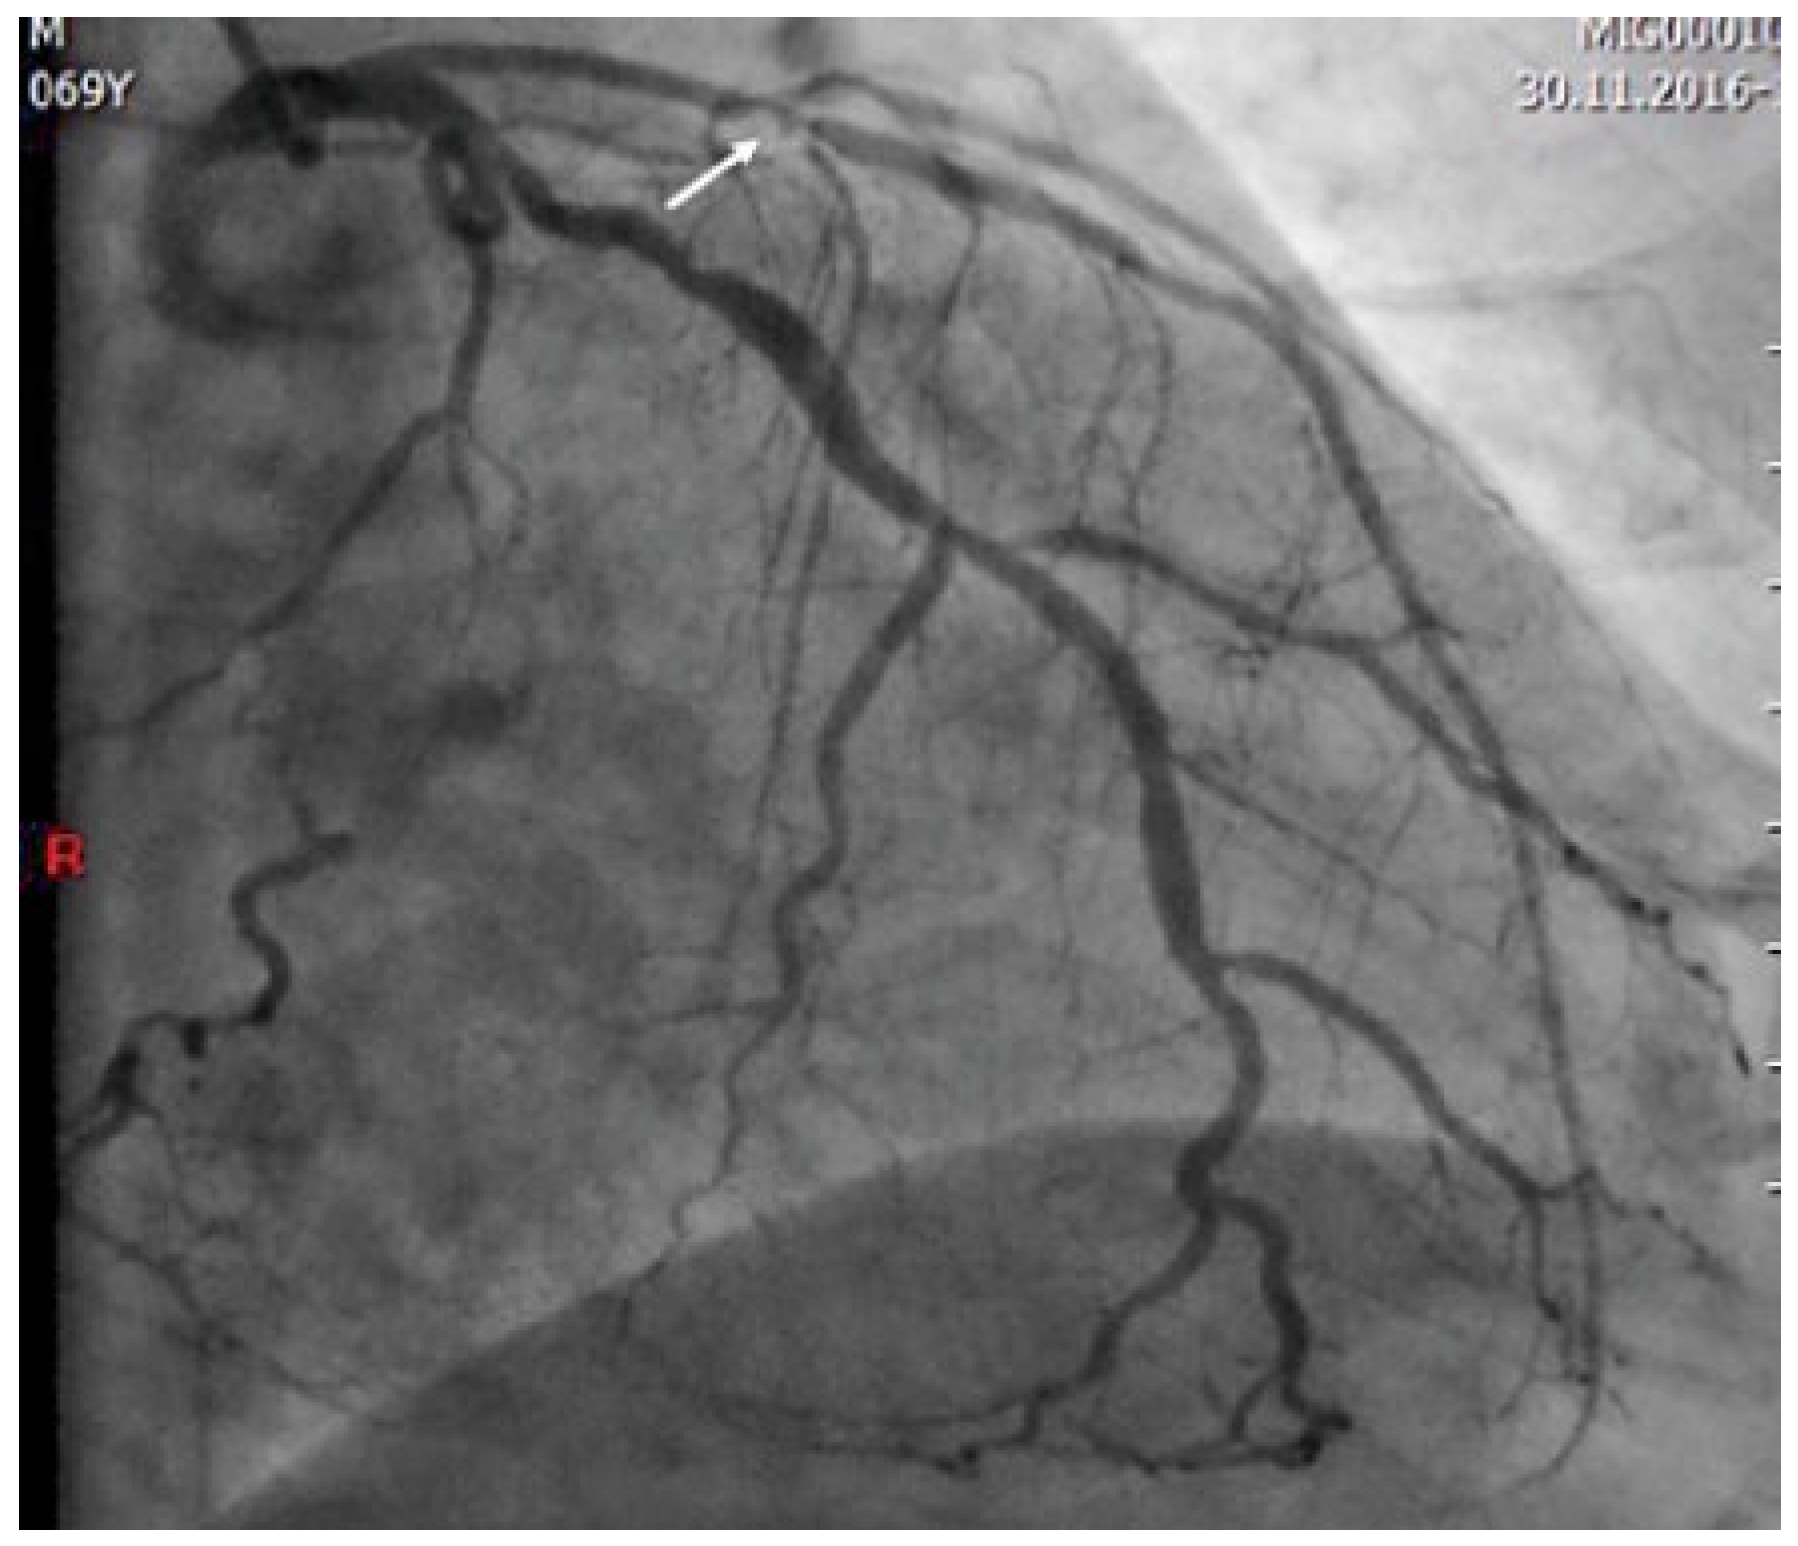

Two types of Wellens’ syndrome are identified. The most common (type I, 75% of cases) is characterised by deep negative T waves in V2–V3 and often in V4. One third of patients present the less common type II, with biphasic T waves in V2–V3 as seen in our patient [6,7]. Echocardiography on the day of presentation showed normal systolic function without regional myocardial motion abnormalities. A second troponin analysis was slightly positive. The patient underwent urgent coronary angiography (12 hours after the first medical contact), which showed severe multivessel coronary artery disease with a severe proximal LAD stenosis involving the ostium of a diagonal branch (Figure 2). Coronary by pass graft surgery was performed and the post-operative period was uneventful. On subsequent echocardiography, the systolic function was normal without regional wall motion abnormalities. Figure 3 shows the ECG after revascularisation.

Figure 2.

Coronary angiography demonstrating the critical proximal LAD stenosis involving the ostium of a diagonal branch (arrow).